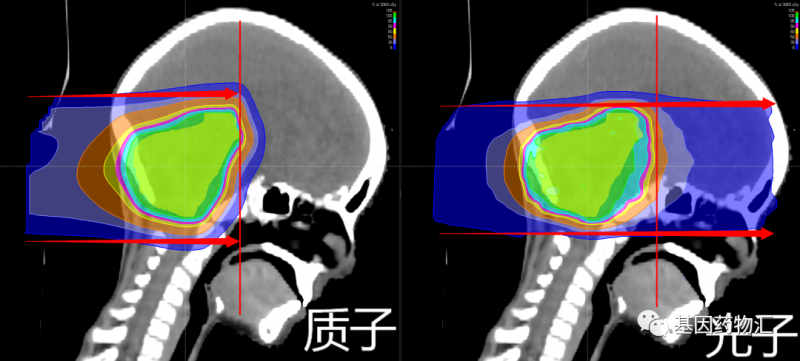

除能量强度外,由于粒子的重量不同,两种射线束还具有不同的特性。质子是相对较重的带正电的粒子,它们会在击中目标时停止。而X射线由光子组成,光子是几乎没有质量的粒子,因此它们会一直穿过身体,包括健康的组织。

在保持病灶部位所受放射剂量一致的情况下,质子治疗方案对于病灶以外的正常组织造成的放射剂量低于光子方案。根据美国临床肿瘤学会(ASCO)的研究数据,质子疗法可以降低靶部位周围组织所受到的放射剂量的60%,并将这些剂量充分应用至病灶部位。

基于质子和质子束本身的特点,比起传统的光子放疗,质子疗法具有一些独特的优势:放射剂量更集中于病灶部位、不良反应更少、安全性更好、二次肿瘤发生率更低、治疗过程中痛苦更少等等。这些特点都很有利于颅内病灶、尤其是儿童患者颅内病灶的治疗。